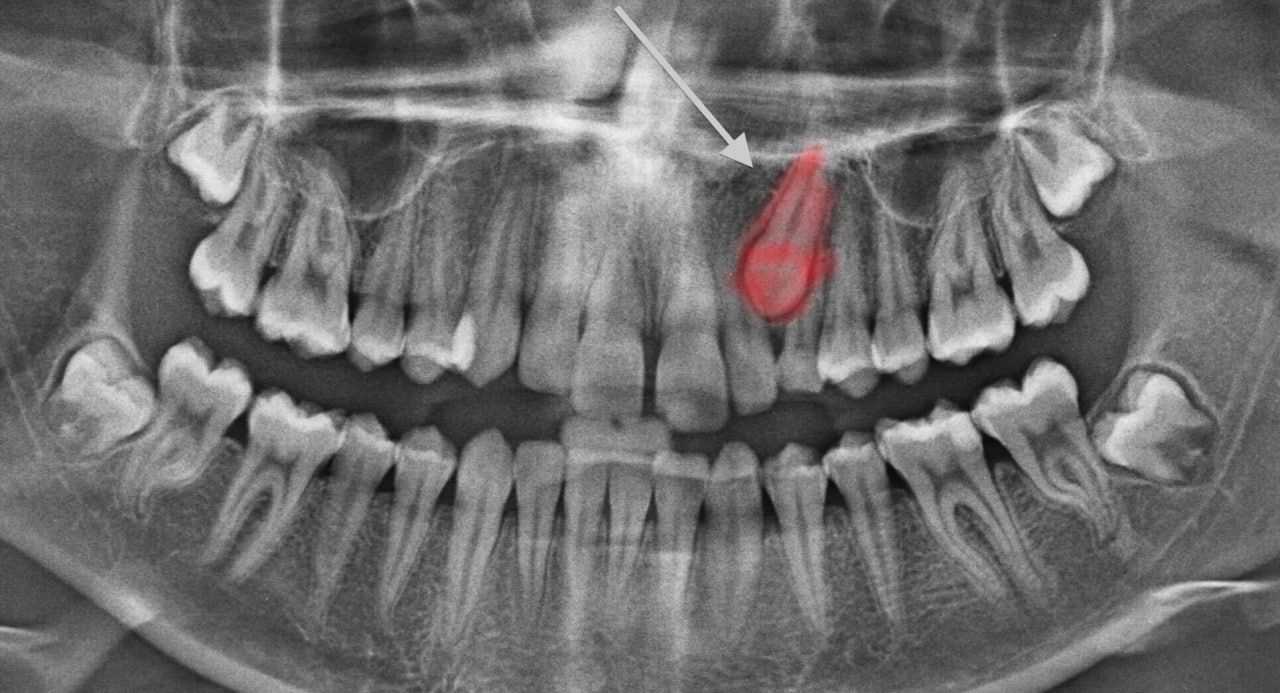

Найважливіше при екстракції – попередня комплексна діагностика. Перед процедурою лікар обов’язково направляє пацієнта на комп’ютерну томографію (КТ).